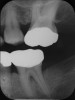

After complete management of moderate to severe periodontitis, including scaling and root planing and in some cases periodontal surgery, subsequent regular periodontal maintenance is reported to prevent tooth loss in up to 85% of patients over a long-term follow-up interval of up to 53 years.6,8 This high success rate of periodontal treatment is comparable to that of dental implants in replacing teeth lost to severe periodontal diseases, highlighting the predictability of maintaining the natural dentition in most patients with periodontal diseases9,10 (Figure 1A and Figure 1B).

Figure 1a  Long-term results of a case involving a 55-year-old woman treated by regenerative periodontal surgery followed by periodontal maintenance every 3 months for 8 years. (A) Radiograph taken in May 2000

Figure 1a

Figure 1b  Long-term results of a case involving a 55-year-old woman treated by regenerative periodontal surgery followed by periodontal maintenance every 3 months for 8 years. (B) radiograph of the same area taken in July 2008.</a></span><P>Figure 1b</P></div>    <div class=